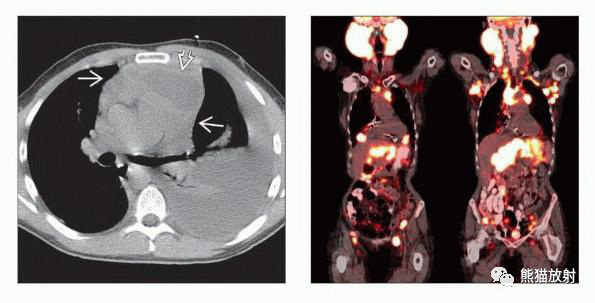

(左) HL,PA胸片显示纵隔增宽,直径大于胸部横径的1/3,与淋巴结肿大一致,提示预后不良。

(右) 同一患者,NECT(上)和PET/CT(下)显示前纵隔密度均匀肿块,FDG明显摄取,气管右旁淋巴结受累。